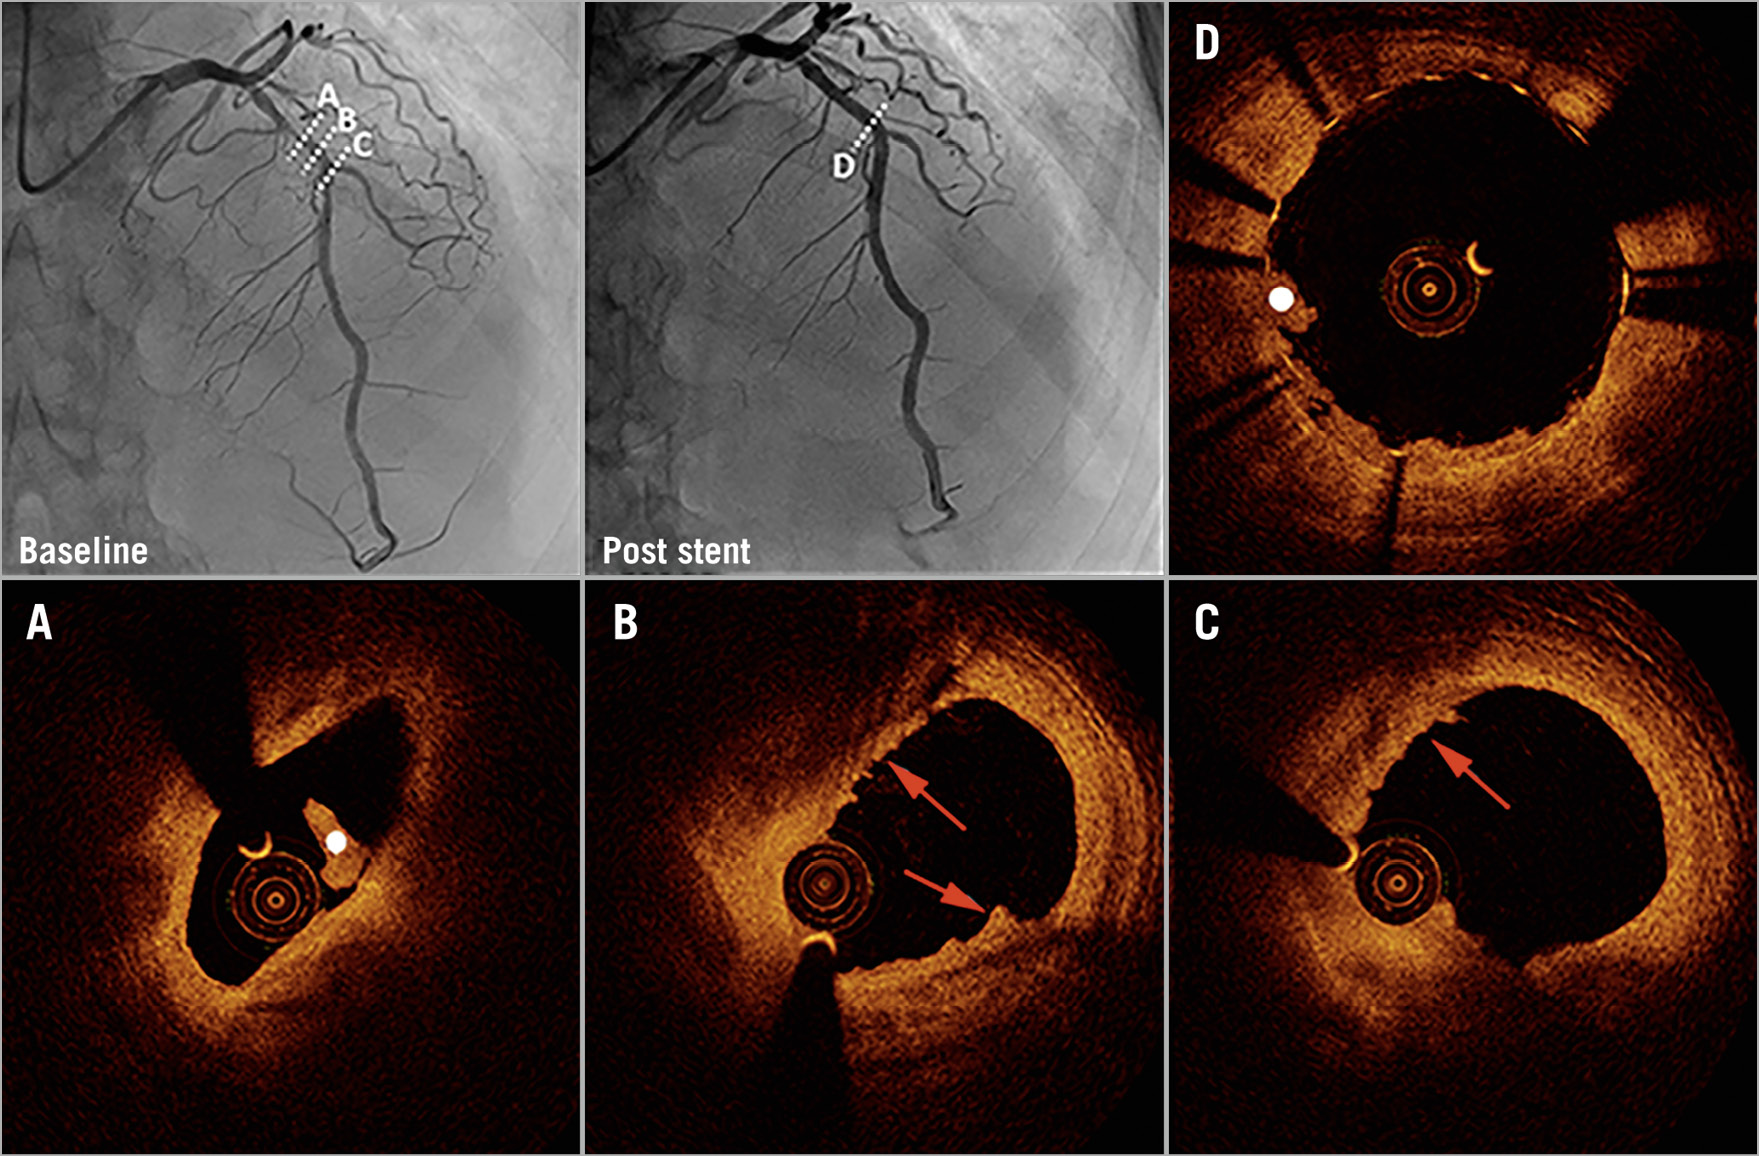

Figure 2. Coronary angiography and optical coherence tomography in early spontaneous reperfusion. Baseline angiography (upper left) shows a patient with TIMI 3 flow. Optical coherence tomography (OCT) shows plaque erosion (red arrows) and white thrombus (white dot) (A-C). Coronary angiography (upper middle) and OCT show imaging of the region after stent implantation (D).